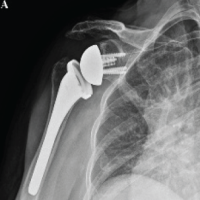

A day care outpatient procedure was planned and performed, lasting around 10 min. The patient was seated with their elbow flexed at 90° and turned inward. Adhering to strict aseptic techniques, the right shoulder area was cleaned, disinfected, and draped. The cyst’s outline was marked with a sterile marker. A No. 1 silk suture was threaded through a cutting needle and inserted into one side of the cyst, emerging from the opposite side. The thick, yellowish, jelly-like fluid observed upon entry indicated that access to the ganglion was successful. The same suture was then re-threaded back through the cyst in the reverse direction, creating a loop within the cyst. Subsequently, a second suture was introduced perpendicularly in a similar manner, again forming a loop inside the cyst in orthogonal directions, forming a cross-stitch pattern to guarantee complete decompression. Once the cystic fluid was drained, a sterile gauze was positioned over the site, and the sutures were secured (Fig. 2a and b).

Figure 2: (a and b) Intraoperative.